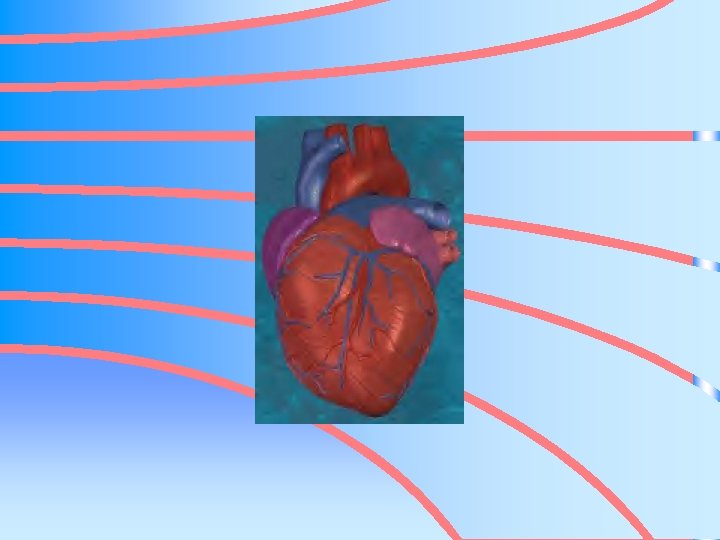

HEART • • MUSCULAR, HOLLOW ORGAN PUMP OF THE BODY SIZE OF CLOSED FIST LOCATED – MEDIASTINAL CAVITY – BETWEEN HEART AND LUNGS – BEHIND STERNUM – ABOVE DIAPHRAGM

THREE LAYERS OF TISSUE • ENDOCARDIUM • MYOCARDIUM • PERICARDIUM

ENDOCARDIUM • SMOOTH LAYER OF CELLS • LINES THE INSIDE OF THE HEART & BLOOD VESSELS • ALLOWS FOR SMOOTH FLOW OF BLOOD

MYOCARDIUM • Thickest layer • muscular middle layer

PERICARDIUM • DOUBLE LAYERED MEMBRANE OR SAC • COVERS THE OUTSIDE OF THE HEART

SEPTUM • MUSCULAR WALL • SEPARATES HEART INTO RIGHT AND LEFT SIDE • PREVENTS BLOOD FROM MOVING BETWEEN THE RIGHT AND LEFT SIDE OF THE HEART • UPPER PART OF SEPTUM CALLED – INTERATRIAL SEPTUM • LOWER PART CALLED – INTERVENTRICULAR SEPTUM

HEART CHAMBERS • FOUR PARTS OR CHAMBERS • TWO UPPER CHAMBERS – ATRIA • TWO LOWER CHAMBERS – VENTRICLES